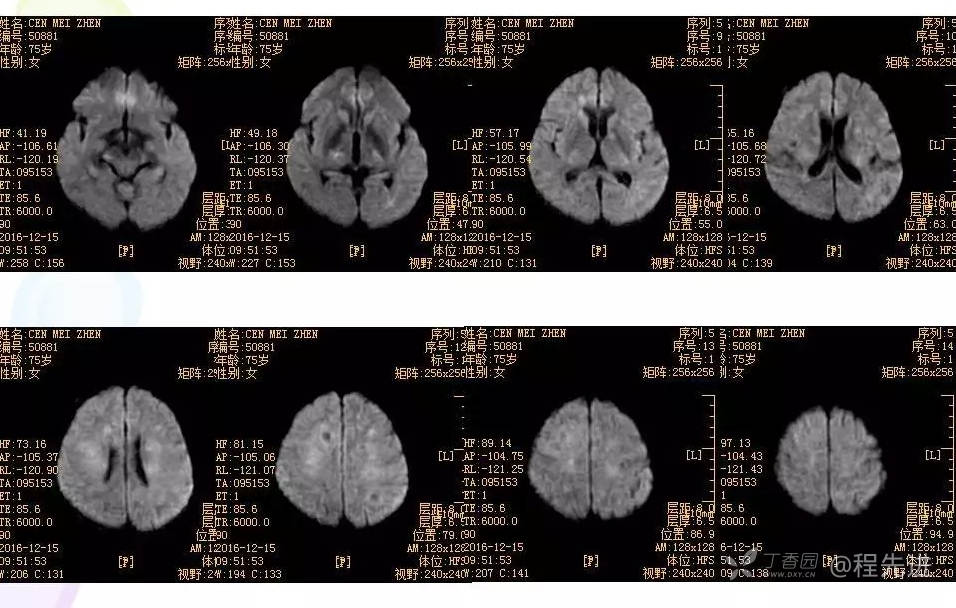

3月特别精彩病例|头晕伴左侧肢体乏力、行走不稳1周【结果已公布】

患者性别:女

患者年龄:75岁

简要病史:头晕伴左侧肢体乏力、行走不稳1周。否认高血压、脑梗塞、肝炎、糖尿病、肺结核病史。否认疫区疫水接触史。